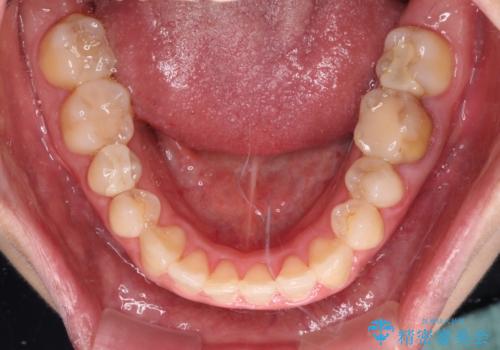

- 前歯の捻れを気にして来院された患者様です。

上顎前歯が捻れて前方に飛び出しており、下顎前歯もそれに沿うようにデコボコとなっていました。

IPR(歯と歯の間を削る処置)によりスペースを獲得して上下前歯のデコボコを改善し、インビザラインにて矯正治療を行うこととしました。